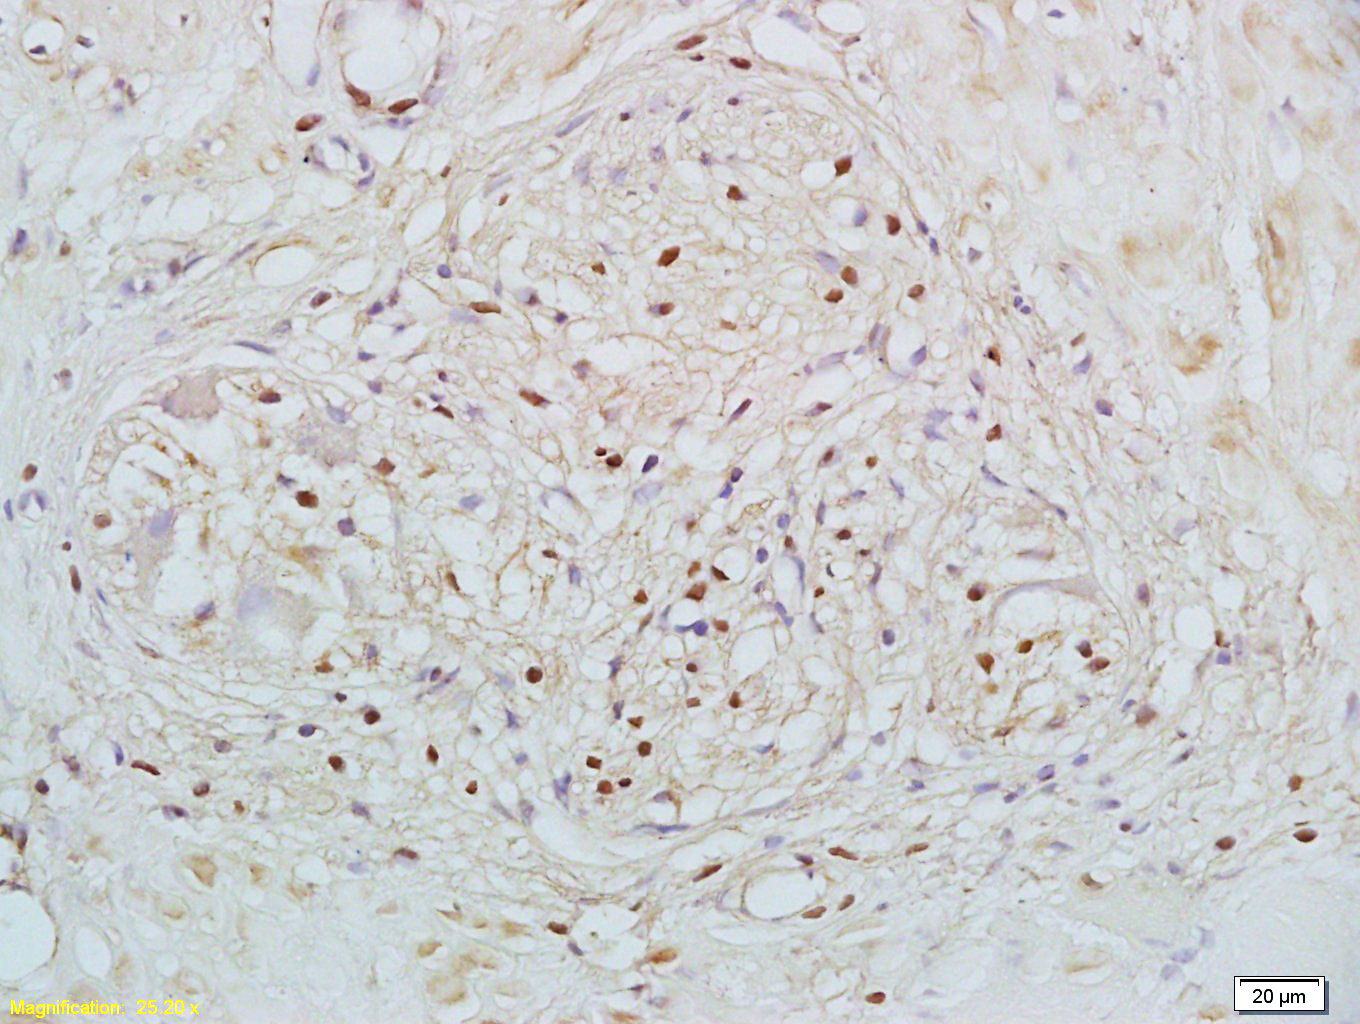

Paraformaldehyde-fixed, paraffin embedded (Human stomach); Antigen retrieval by boiling in sodium citrate buffer (pH6.0) for 15min; Block endogenous peroxidase by 3% hydrogen peroxide for 20 minutes; Blocking buffer (normal goat serum) at 37°C for 30min; Antibody incubation with (RXRB) Polyclonal Antibody, Unconjugated (bs-6219R) at 1:500 overnight at 4°C, followed by a conjugated secondary (sp-0023) for 20 minutes and DAB staining.